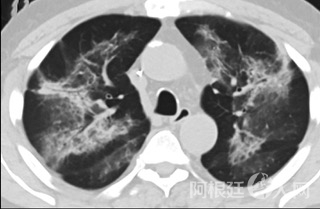

疑点二,中国科研工作者从60篇研究论文中筛选出142位电子烟肺炎患者的250张影像图片,邀请3位放射科权威专家,对上述全部影像图片、相关病人临床信息以及文献原文进行了仔细全面研究与审查,又有了新的发现。

6天后的轴向CT平扫图像显示毛玻璃影变为实变和轻度结构扭曲。(同一病人CT影像)